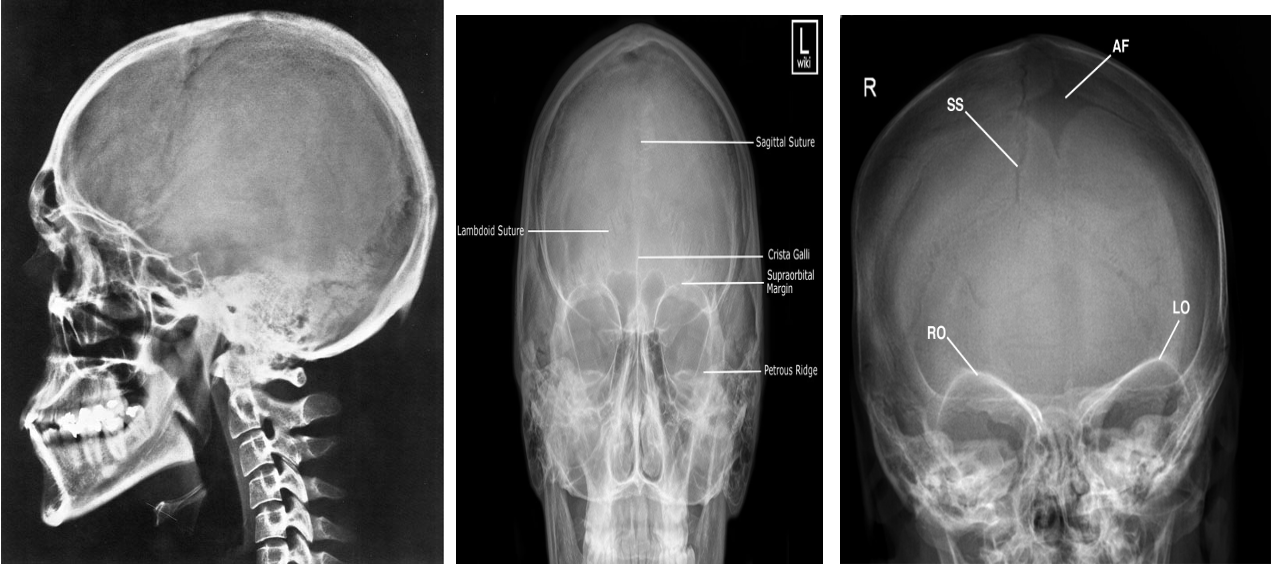

Skull radiographs are rarely performed except as part of skeletal surveys in suspected non-accidental injury or myeloma.

X-ray skull: May be used if CT is not available in skull fractures, however, depressed skull fractures may be difficult to visualize by X-ray skull and it cannot be used to evaluate for intracranial injuries